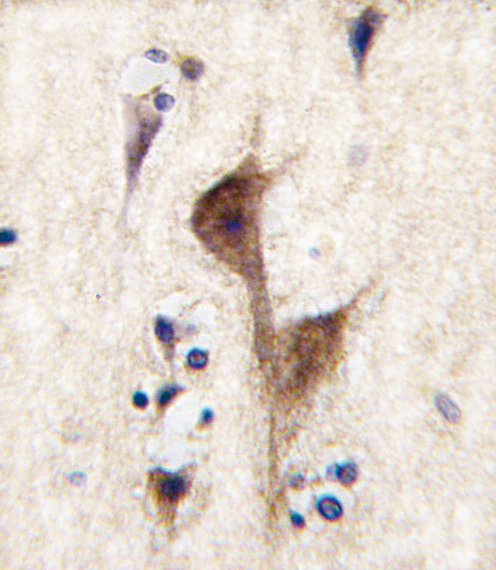

Formalin-fixed and paraffin-embedded human brain tissue reacted with HRH3 antibody (C-term), which was peroxidase-conjugated to the secondary antibody, followed by DAB staining. This data demonstrates the use of this antibody for immunohistochemistry; clinical relevance has not been evaluated. |